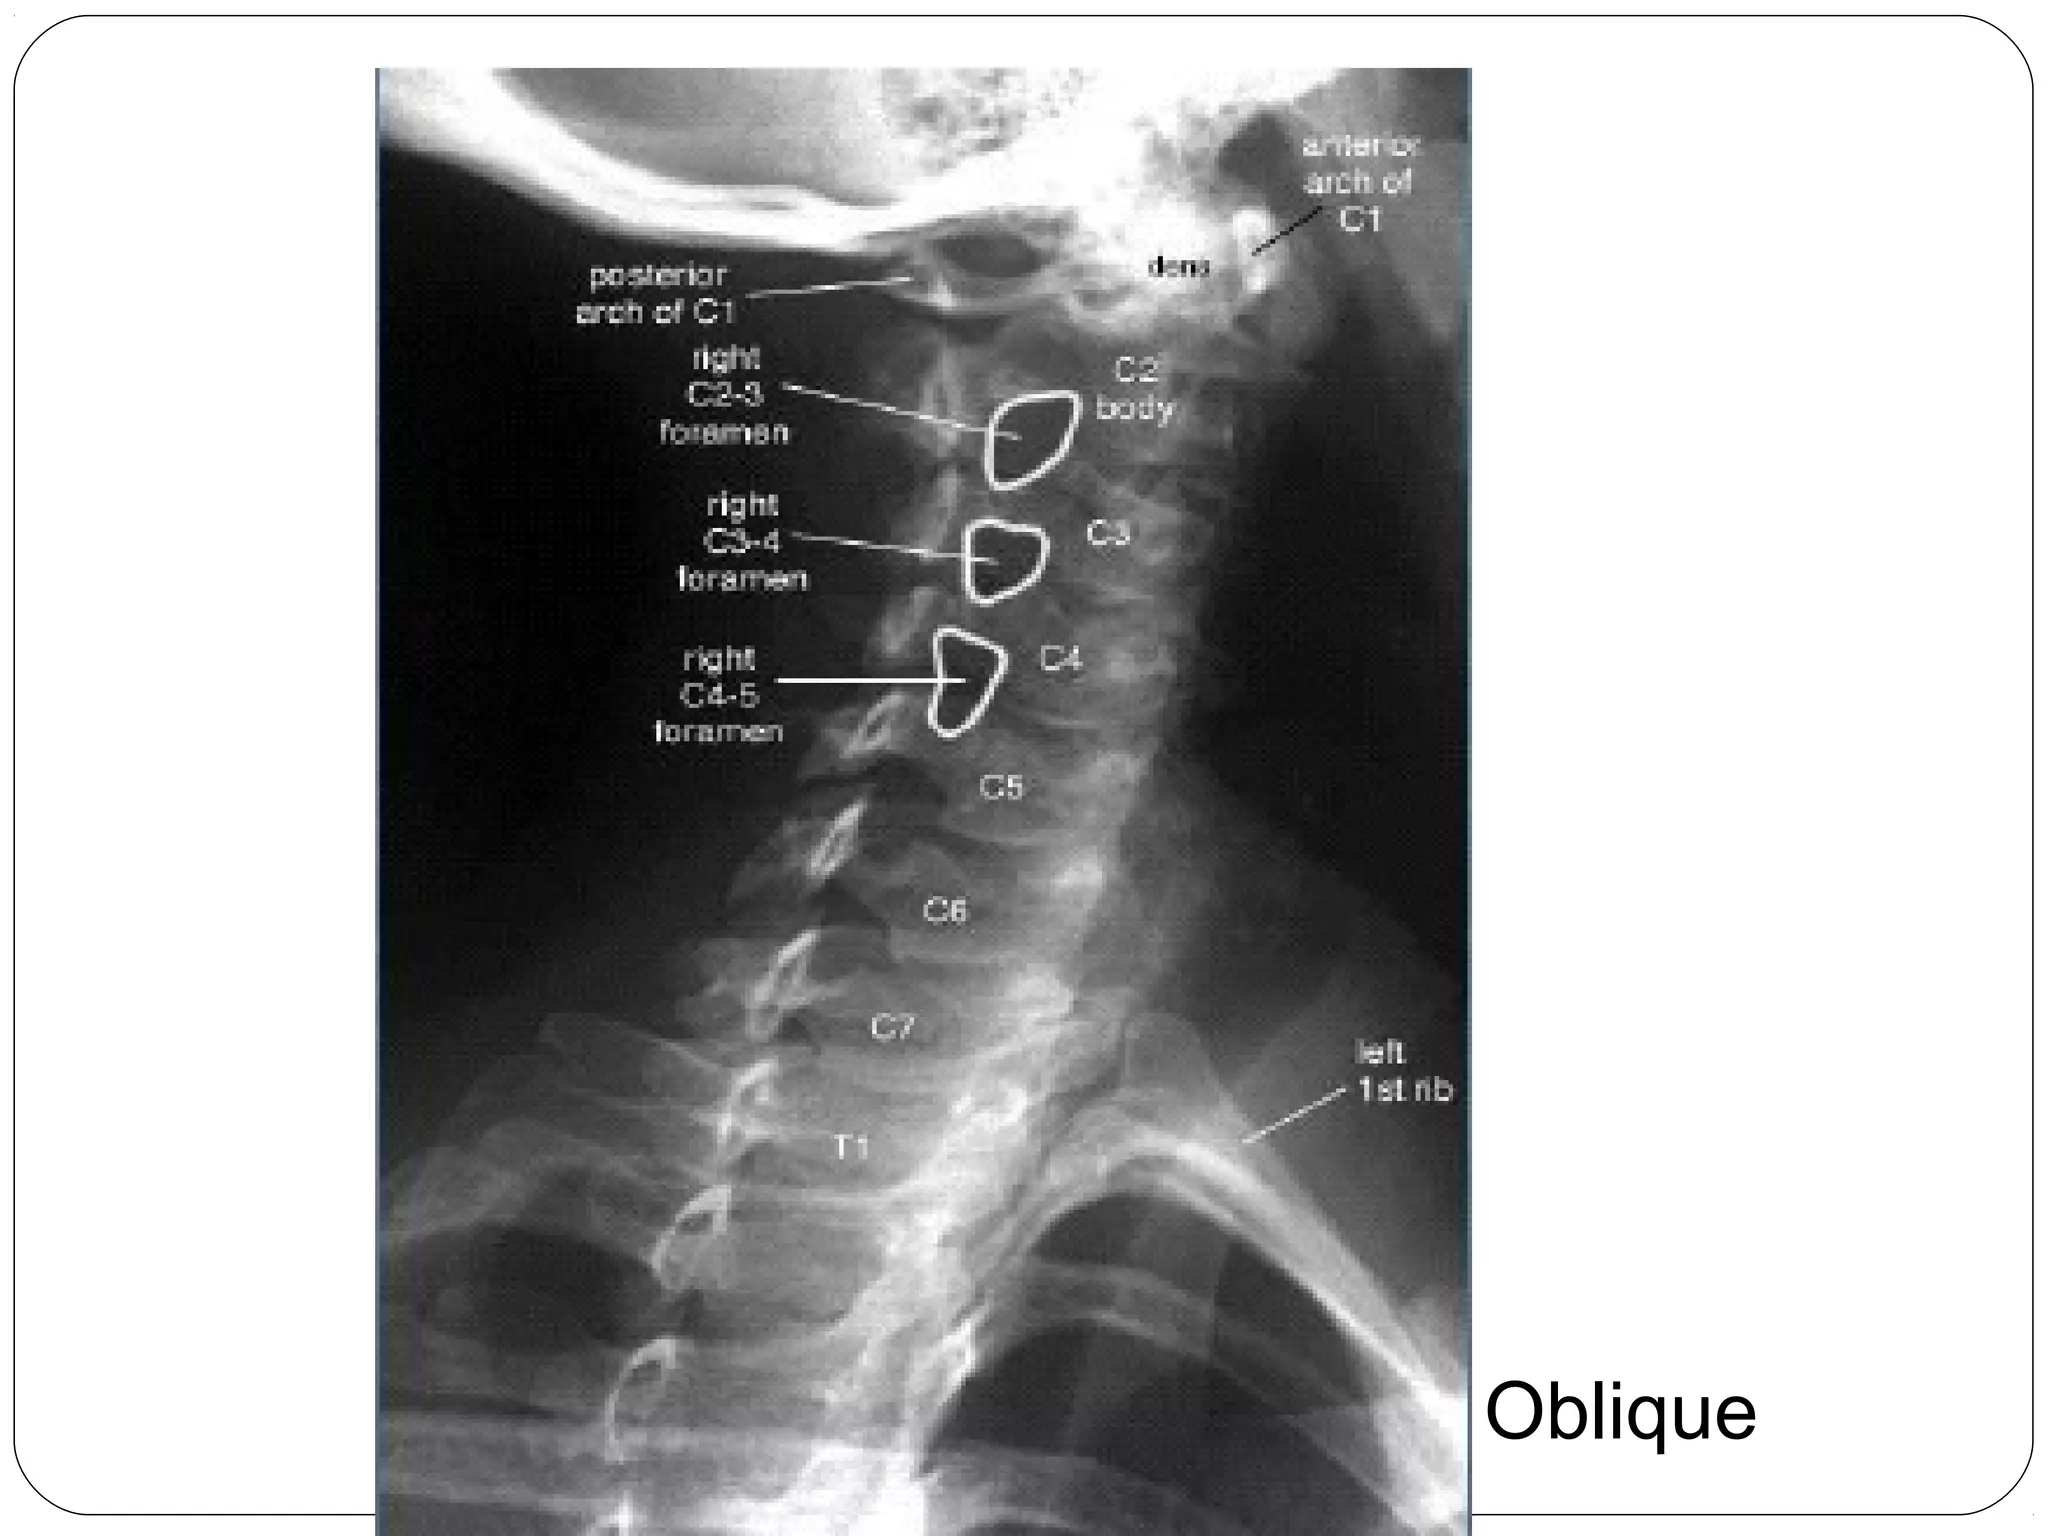

Views

Lateral

Oblique

Lumbar Spine, Oblique View

“SCOTTY DOG”